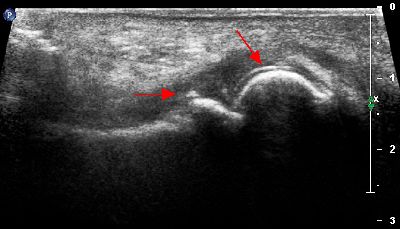

Esostosi subungueale in paziente con onicectomia totale esostosi subunguelae